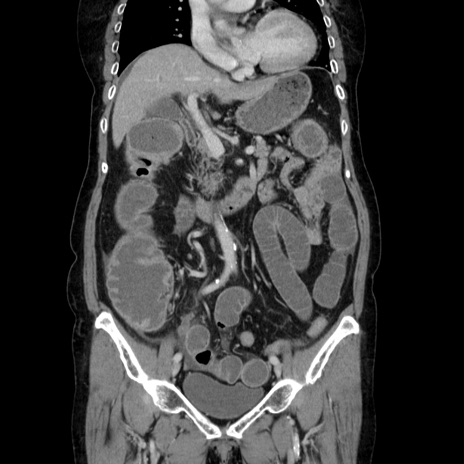

症例5(冠状断像)

【症例】70歳代女性

【主訴】お腹が張る

【現病歴】1週間くらい前から腹部膨満の自覚あり。昨日夜から増悪したため、本日救急外来受診。

【身体所見】意識清明、BT 36.5℃、BP 165/106mmHg、HR 80bpm、SpO2 98%、腹部:膨満、軟、自発痛・圧痛なし、触診にて不快感あり、腸蠕動音:減弱

【データ】WBC 12600、CRP 1.04